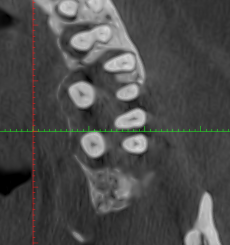

El CBCT permite una visualización tridimensional del hueso, aportando información clave que no se obtiene con estudios 2D:

- Evaluación precisa de la altura y volumen óseo alrededor de cada diente.

- Identificación de defectos óseos verticales y horizontales.

- Análisis de pérdida ósea en caras vestibulares y linguales.

- Detección de zonas con riesgo de movilidad o pérdida dental.

Esta información resulta esencial para establecer un diagnóstico periodontal realista y planificar el tratamiento adecuado.

Importancia del CBCT en la planificación del tratamiento

En pacientes con periodontitis avanzada, el CBCT es especialmente útil antes de:

- Decidir la conservación o extracción de dientes comprometidos.